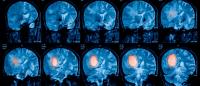

Columbia University will be among the first to enroll patients with glioblastoma—the most common primary brain cancer in adults—in a new type of clinical trial that could speed the identification and development of the most promising therapies for the disease. Instead of evaluating each therapy in its own separate clinical trial, GBM AGILE (Adaptive Global Innovative Learning Environment) is designed to evaluate several drug candidates at once.

Each year, about 12,000 people in the United States are diagnosed with glioblastoma. There are few treatments for the disease, and none are curative. Half of patients succumb to the disease within 15 months of diagnosis.

“Unfortunately, glioblastoma is an aggressive brain cancer, and new therapies have brought only incremental survival benefits,” says Andrew Lassman, MD, chief of neuro-oncology at Columbia University Irving Medical Center and a GBM AGILE investigator. “Even a small tumor can cause devastating neurological problems depending on its location in the brain. The standard of care just doesn’t work for most patients with glioblastoma.”